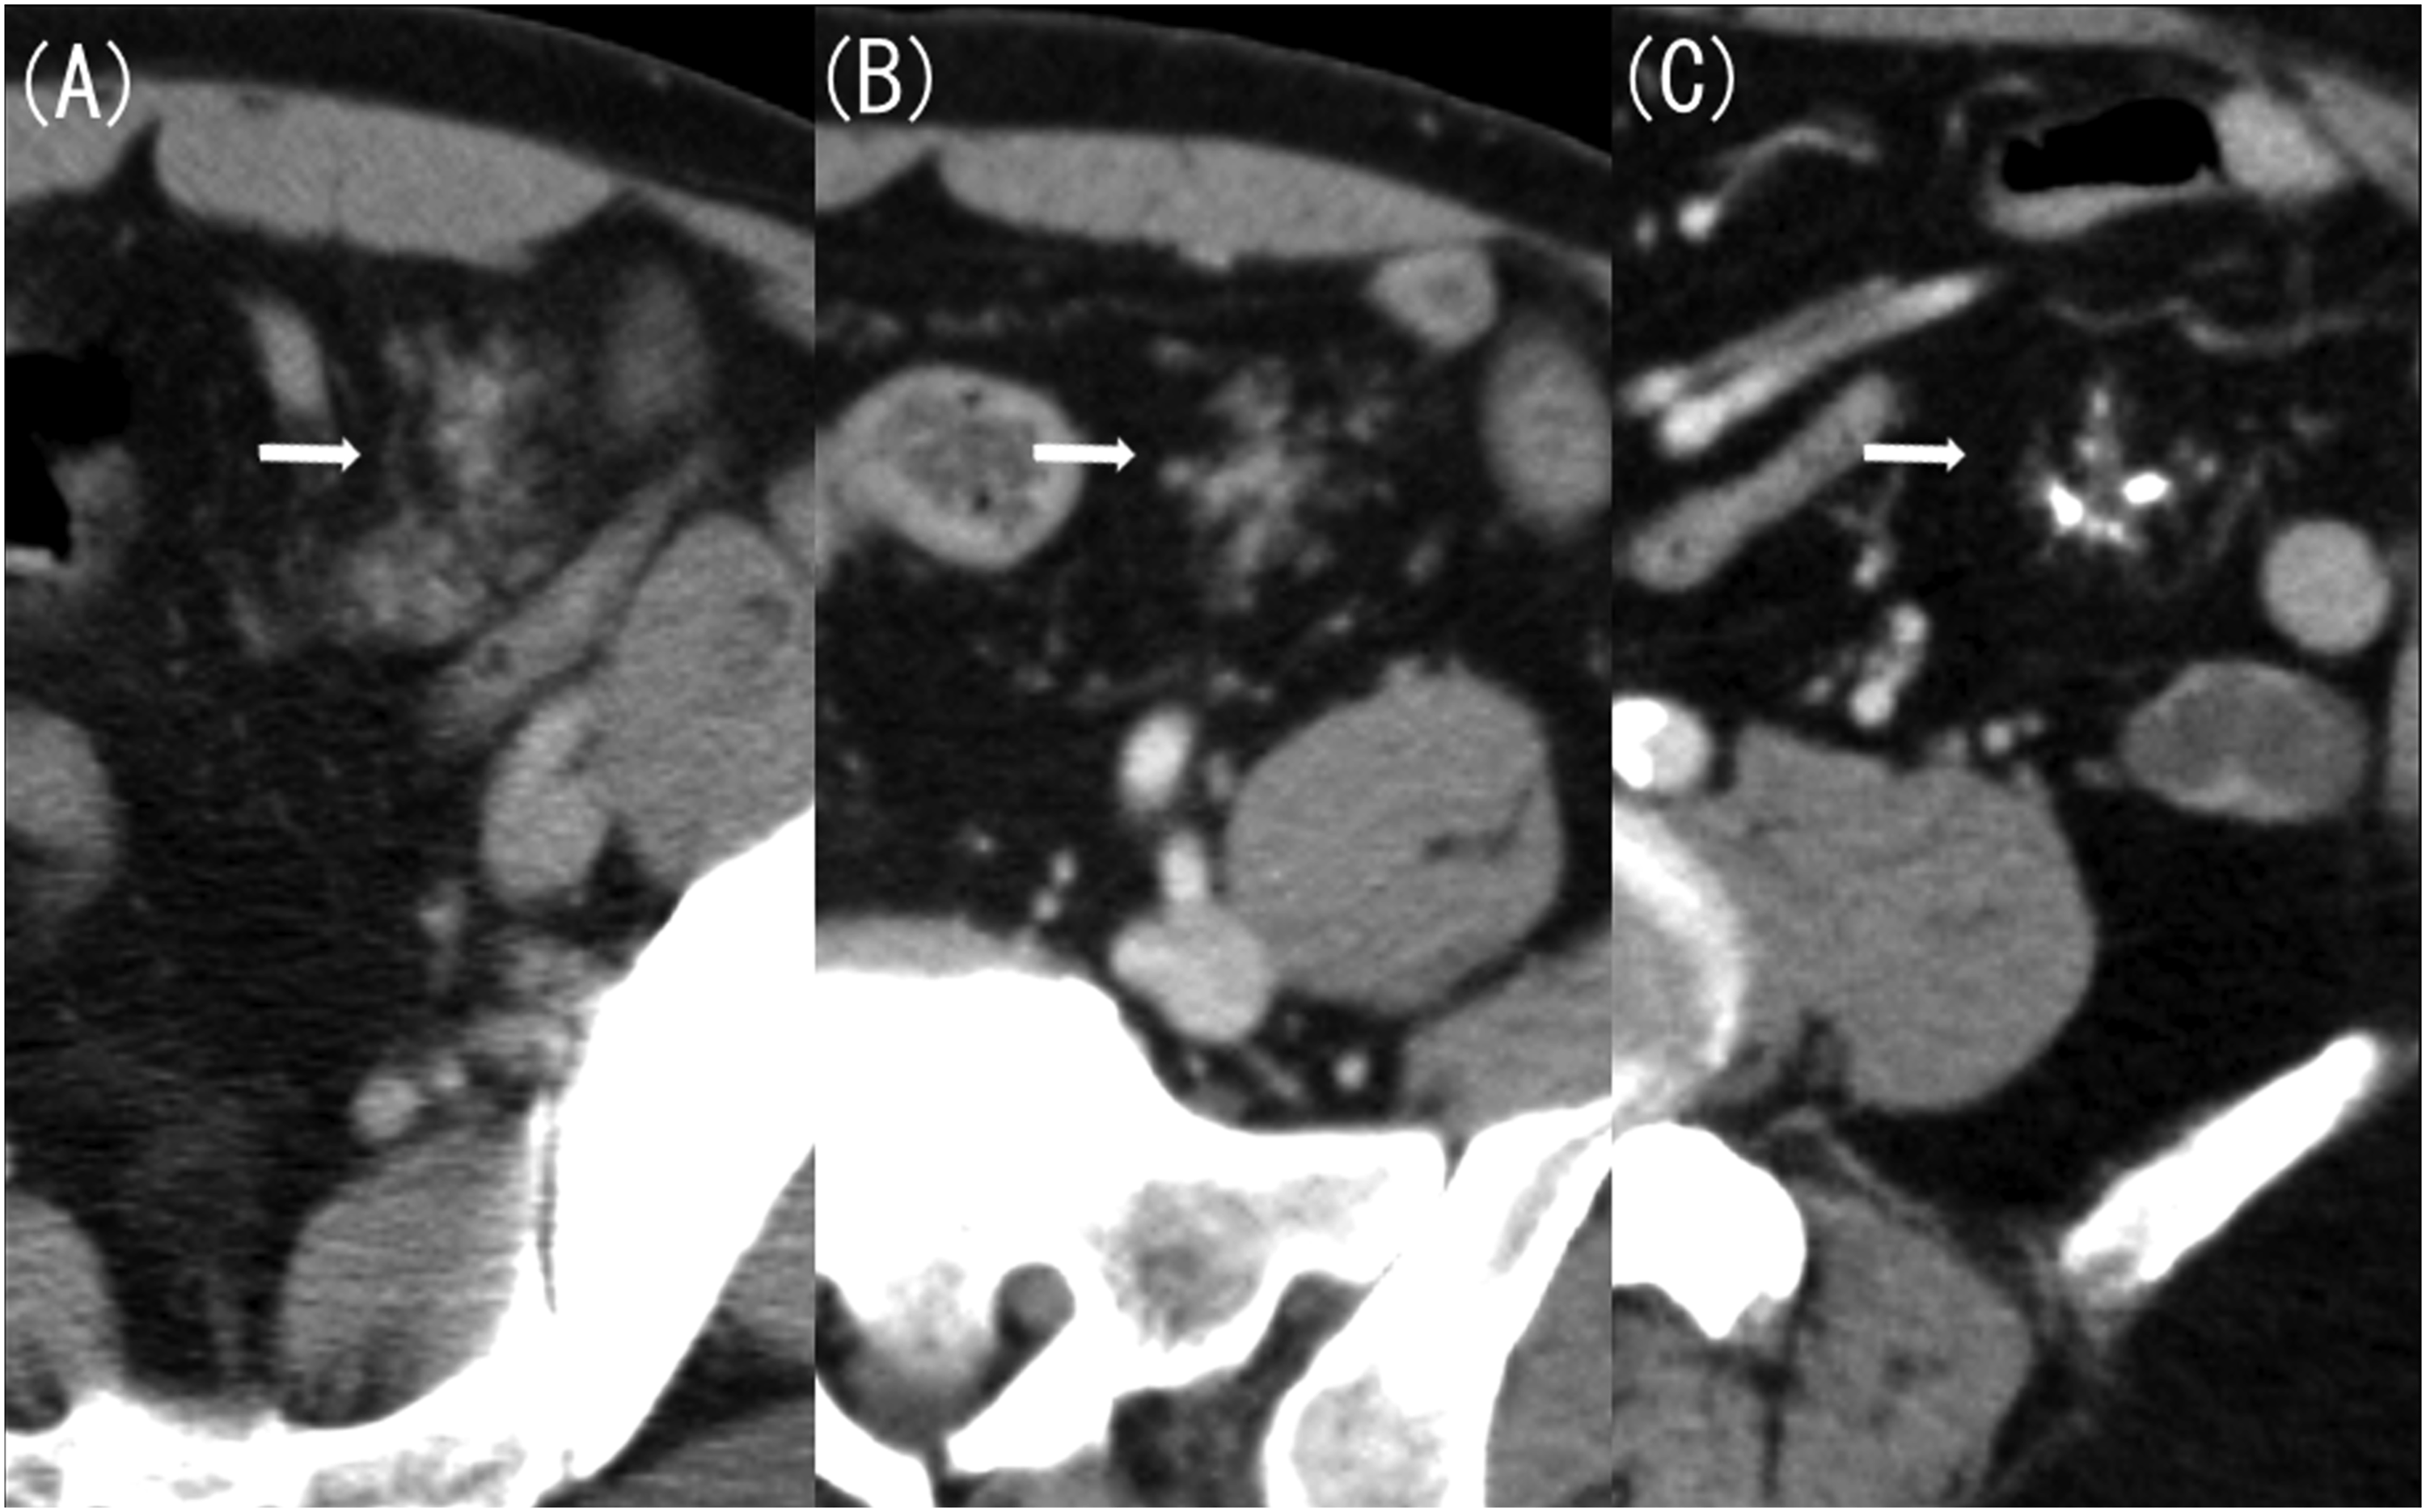

Next, we considered Meckel’s diverticulitis and confirmed the presence of Meckel’s diverticulum on previous CT scans. Contrast-enhanced CT performed 20 years ago revealed a 4 cm-long and 1.5 cm-wide lobulated structure in the left mesentery of the pelvis, resembling the pancreas (Figure 2(a)). CT scan performed 10 years ago showed that this structure had shrunk, appearing similar to an atrophied pancreas (Figure 2(b)). In a CT scan taken 4 years ago, it had further shrunk, with numerous calcifications (Figure 2(c)). The imaging findings were similar to a pancreatitis progressing to a chronic type observed in original pancreas. Additionally, the CT scan taken this time revealed dilatation of the luminal structure that corresponded to the main pancreatic duct (Figure 3(a)) and a stone being confined to the small intestine side (Figure 3(b)). This image finding indicated an acute exacerbation caused by pancreatic stone incarceration that typically occurs in chronic pancreatitis. The location of this structure was in the lower left abdomen on the CT scans taken 20 and 10 years ago, in the left abdomen on the CT scan taken 4 years ago, and in the lower right abdomen on the CT scan taken this time. A CT scan taken 20 years ago showed signs of acute pancreatitis of the native pancreas, including swelling and increased fat concentration in the surrounding area. However, there has been no change in size or shape of the native pancreas since the CT scan taken 10 years ago. (A) Contrast-enhanced computed tomography (CT) image taken 20 years ago (axial image, late phase). (B) Contrast-enhanced CT image taken 10 years ago (axial image, late phase). (C) Contrast-enhanced CT image taken 4 years ago (axial image, late phase). Contrast-enhanced CT taken 20 years ago revealed a pancreas-like lobulated structure measuring 4 cm-long and 1.5 cm-wide located in the left mesentery of the pelvis (A, arrow). Contrast-enhanced CT taken 10 years ago showed that the structure had shrunk, resembling an atrophied pancreas (B, arrow). Additionally, contrast-enhanced CT performed 4 years ago showed that the structure had further shrunk, with numerous calcifications (C, arrow). (A) Contrast-enhanced computed tomography (CT) image taken this time (coronal image, late phase). (B) Contrast-enhanced CT image taken this time (sagittal image, late phase). Compared with the CT result obtained 4 years ago, the luminal structure corresponding to the main pancreatic duct was dilated, with a stone confined to the small intestine side.